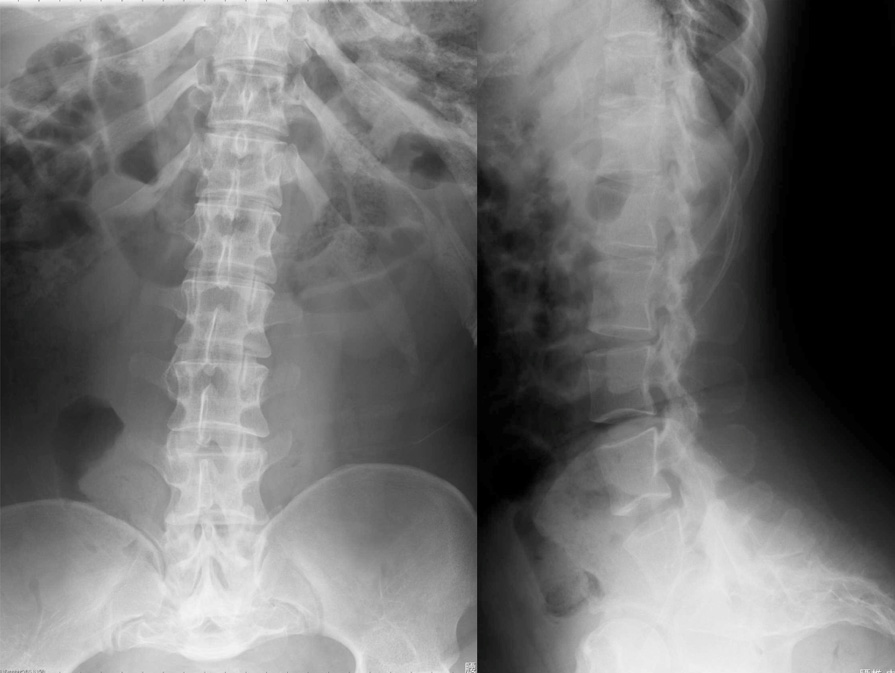

- 図1 腰椎2方向レントゲン

椎弓根や椎弓根間距離の短縮による脊柱管の狭窄。椎体後縁の陥凹 posterior scalloping。

著しい腰仙部の前弯

- 脊椎(正面、側面)

椎弓の短縮のために脊柱管は狭窄し,脳脊髄液の拍動に対するリモデリングの異常の結果、椎体後縁は後方凹となる(posterior scalloping)。椎体終板の軟骨内骨化遅延のために, 椎体辺縁は丸みを帯びており,posterior scalloping と合わせて,椎体は小弾丸様bullet-shapedに見える。椎体の上下径は短縮しているが,posterior scallopingによる前後径の減少のために椎体は扁平には見えない。

正常の腰椎椎弓根間距離は,頭側から尾側に向かう につれて広くなるが,逆に,尾側に向かうにつれて狭くなる(interpediculate narrowing)。これは診断上重要な所見であるが,乳児期には目立たないので,注意が必要である。